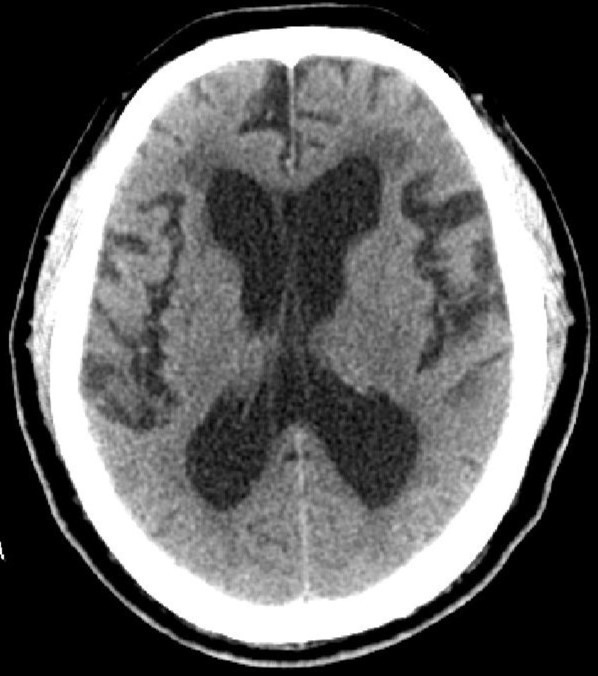

因为脑脊液的分泌、或循环、或吸收过程中出现障碍,则会产生脑积水。脑积水致脑脊液的容积增大,导致脑血流量及脑组织受压并容积减少。临床分类多样:婴幼儿脑积水和成人脑积水;高压性脑积水和常压性脑积水;脑室内脑积水和脑外脑积水;症状性脑积水和无症状性脑积水;进行性脑积水和静止性脑积水。比较常用的是按病因分类:交通性脑积水和阻塞性脑积水。其中交通性脑积水病因:脑脊液吸收功能障碍、蛛网膜颗粒发育不良、脑脊液成份改变或浓缩及脑脊液分泌过多;阻塞性脑积水病因:中脑水管狭窄或闭塞、Dandy-Walker综合征、小脑扁桃体下疝畸形、炎症或出血、颅内占位性病变等。临床症状:婴幼儿有发育延迟、头颅增大、行走障碍等;成人可有神志及精神变差、记忆力下降、头痛头晕、行走困难或二便失控等。头颅CTMR可以明确诊断及辨别病因。治疗主要以手术治疗为主。绝大多数患者愈合良好。(神经外科 龙青山)

正常头颅CT          头颅CT示脑积水